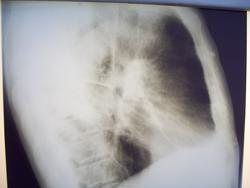

В феврале 2012 на ФГ обратился пациент Кл-в 80 лет, кашель, температура - нормальная.

Взял на Р-скопию.

Предварительный диагноз - постпневмонический фиброз, бессимптомная правосторонняя пневмония. Направлен в страционар. Проведено КГ ОГК

По заключению специалиста - зона консолидации легочной ткани ы S6 сегменте правого легкого может соответствовать БАР, либо хр пневмонии. При выписке 20.04.12 инфильтративные изменения уменьшились

Но 16.08.12 на контрольных ФГ и РГ получилось такое:

Что это может быть?

Конечно,может и хронич пневмония снова обострилась ,но больше данных за центральный рак нужны томограммы

Очень похоже на ценральный рак, а вот в самом лёгком что? Может быть и мтс, и параканкрозная пневмония.

ц рак с параканкрозным воспалением

по КТ? Да кто ж его знает. По 2-м кадрам ничего не скажешь, кроме того, что имеется патологическая плотность в S6 справа.